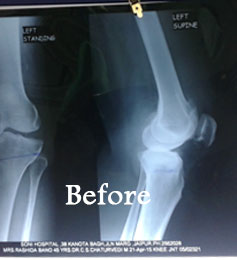

Knee Replacement ( oprated 12 Years Back)

Bilateral knee replacement

Biletur Knee replacement

Biletur knee replacment

Knee rplacement after 5 year